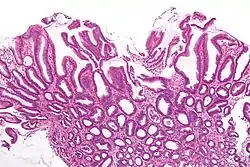

| Micrograph of a reactive gastropathy. H&E stain. | |

- Foveolar hyperplasia (black arrow), as a tortuosity in the "neck" region of the gastric glands.

- Scant or minimal inflammatory cells (white arrow), i.e. lack of large numbers of neutrophils and plasma cells..

- Smooth muscle hyperplasia in the lamina propria (in black oval).

The diagnosis is by examination of tissue, e.g. a stomach biopsy.

Low mag.